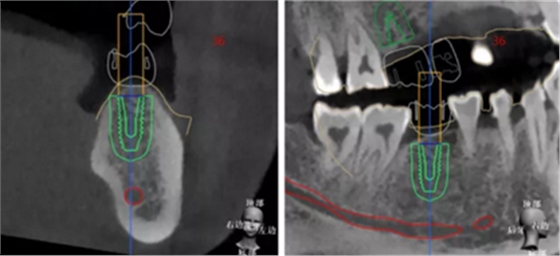

繪制下頜神經(jīng)管

設(shè)計植入5顆種植體

種植規(guī)劃與術(shù)后CBCT影像對比